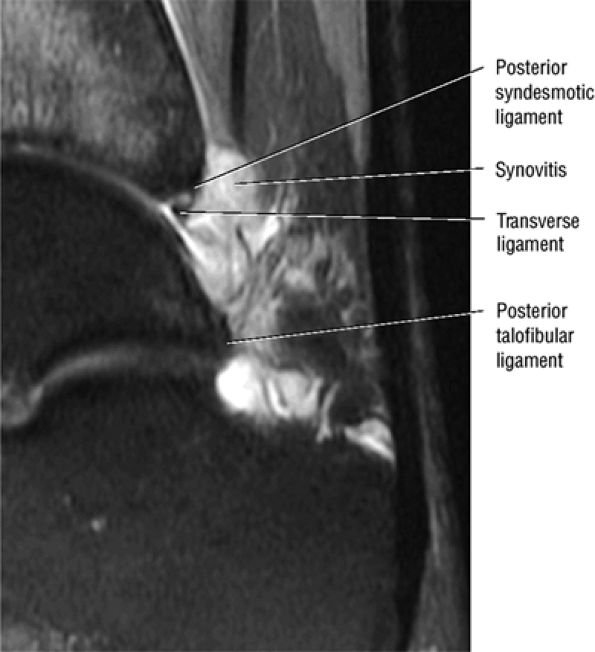

The syndesmotic ligaments consist of the anterior syndesmotic or anterior inferior tibiofibular ligament and the posterior syndesmotic or posterior inferior tibiofibular ligament, the interosseous membrane, and the transverse tibiofibular ligament.

The transverse tibiofibular ligament represents the posterior labrum of the ankle and projects inferior to the posterior tibial margin.

The tibial slip is the posterior intermalleolar ligament.